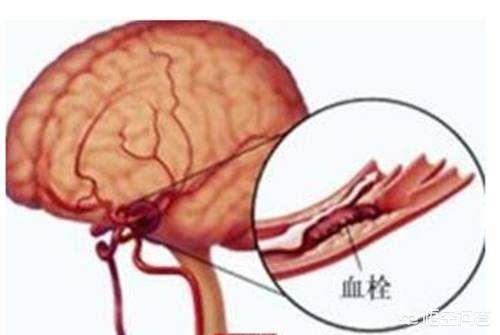

水道管が錆びたり、老朽化したり、汚れが溜まって管腔が狭くなったり、あるいは詰まったりすると、水は上の階まで流れなくなる。想像してみてほしい。本来10世帯に供給されていた水が、水流が細くなったために1世帯しか使えなくなり、他の9世帯が水不足の影響を受ける。

人体を例にとって言えば、水道管の老化は動脈硬化のようなもので、動脈硬化がプラークを生成するのは「さび色の斑点」、「汚れ」のようなものだ。

違いは、プラークが破裂して血栓症を促進する可能性があることで、これが心血管疾患の急性発作の原因である。

実際、血栓症は防御機構である:

例えば、皮膚が破れて出血した場合、出血は自動的に止まるが、これは血栓症の結果である。 血栓が形成され、破れを塞ぐことで出血が止まるのである。しかし、この破断は血管のプラーク上で起こり、破断した場所から自ら修復して血栓が形成されるが、血管局所では限られたスペースしかないため、血管の局所的な狭窄、あるいは閉塞を引き起こす。

頸動脈は、重度のプラーク、つまり不安定プラークが発生すると、一度破裂したプラークが血栓を形成し、この血栓が脳血管に流れて脳血管を閉塞し、脳梗塞を引き起こす。